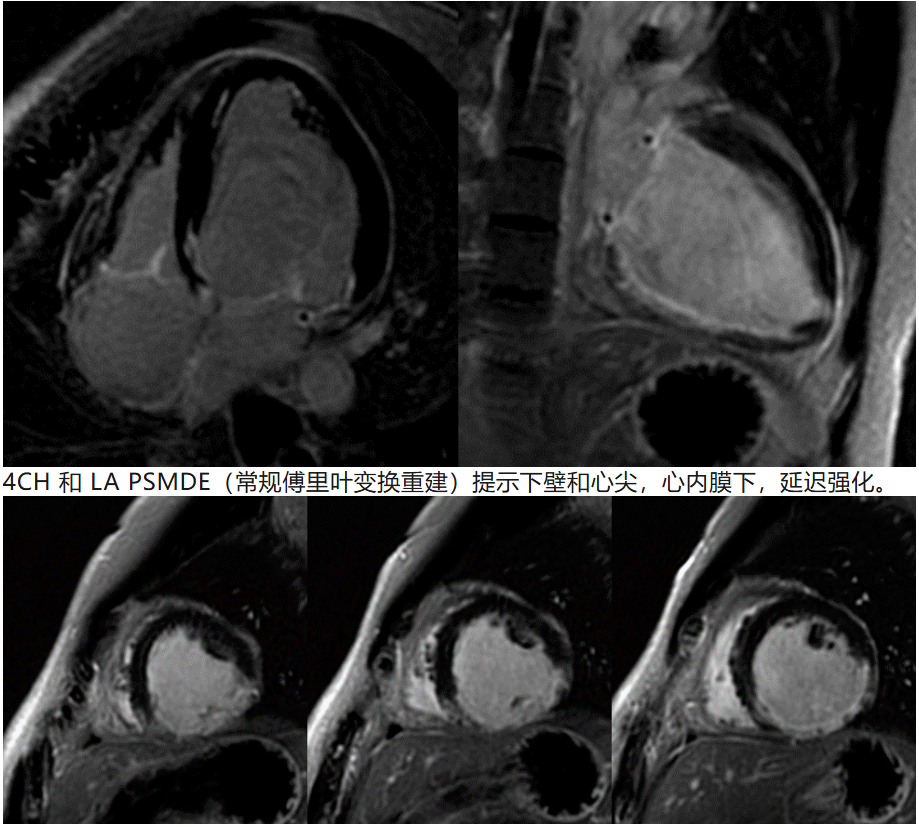

正常心肌:1231ms,病变心肌:1310ms。略有升高。且进一步提示下壁和下侧壁壁薄。2.4 心肌延迟强化(PSMDE)

SA PSMDE(常规傅里叶变换重建)进一步提示下间隔壁,下壁,下侧壁延迟强化,范围超过心肌厚度的50%,提示患者透壁性心肌梗死。这时候,有必要结合病史,理性反推求医过程: 主诉:心脏术后1年余,活动后胸闷1年。 现病史:缘于入院前1年余因“二尖瓣关闭不全”于外院行“二尖瓣成形”,术顺,术后规律服药,1年前无明显诱因出现胸闷、气促,爬3层楼即出现症状,休息后稍缓解,无胸痛、心悸,无端坐呼吸、咳粉红色泡沫样痰、无夜间阵发性呼吸困难,无腹胀、眼黄、尿黄、肢体浮肿,无畏冷、发热、无黑膘、晕厥,无食欲减退、消瘦,就诊外院完善相关检查后诊断“心力衰竭”,予诺欣妥、信他乐克、螺内酯、达格列净等药物治疗,上述症状仍反复发作,今为进一步治疗就诊我院查心脏彩超:二尖瓣成形术后;二尖瓣轻度返流,左室收缩功能重度减退,EF:28.9%,为进一步诊治,门诊拟“心力衰竭”收治入院。自发病以来,精神、食欲、睡眠尚可,二便正常, 体重无明显改变。 既往史:平素体质一般,否认“高血压、糖尿病、冠心病”等慢性病史,否认肝炎、结核、菌痢、伤寒等传染病史,否认其他手术、输血、外伤史,否认过敏史,预防接种按时完成。 个人史:生于原籍,否认长期外地居住史,否认疫区居留史,否认特殊化学品及放射线接触 史。否认吸烟、饮酒史。 婚育史:已婚未育,配偶体健。 家族史:否认家族中类似疾病史。否认家族中“血友病”等遗传性疾病史及"糖尿病、恶性肿瘤”等遗传倾向性疾病史。否认家族中´病毒性肝炎、结核病、伤寒、痢疾”等传染病史 (1)一年前,心衰症状出现:无明显诱因,爬三层楼出现胸闷气促; 意味着一年前,可能的诊断是二尖瓣关闭不全导致心衰。所以治疗手段是二尖瓣成形术,术后规律服药。 面临的困境是目前活动后胸闷。B超提示LVEF = 28.9%。本次MR检查提示LVEF = 43%。本次MR检查提示患者下侧壁、下壁和下间隔壁透壁性心肌梗死,黑血DIR FSE提示心肌无水肿,所以这大概率是一个陈旧性的心肌梗死。2.5 PSMDE基于deep learning recon的重建